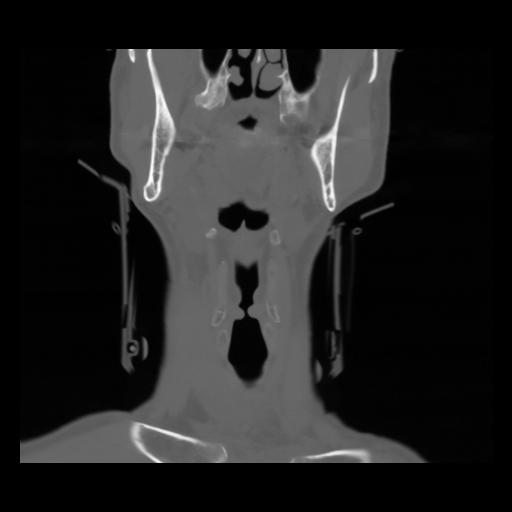

13 P.BLANDAS,,Coronal,2.000,P.BLANDAS,Coronal,